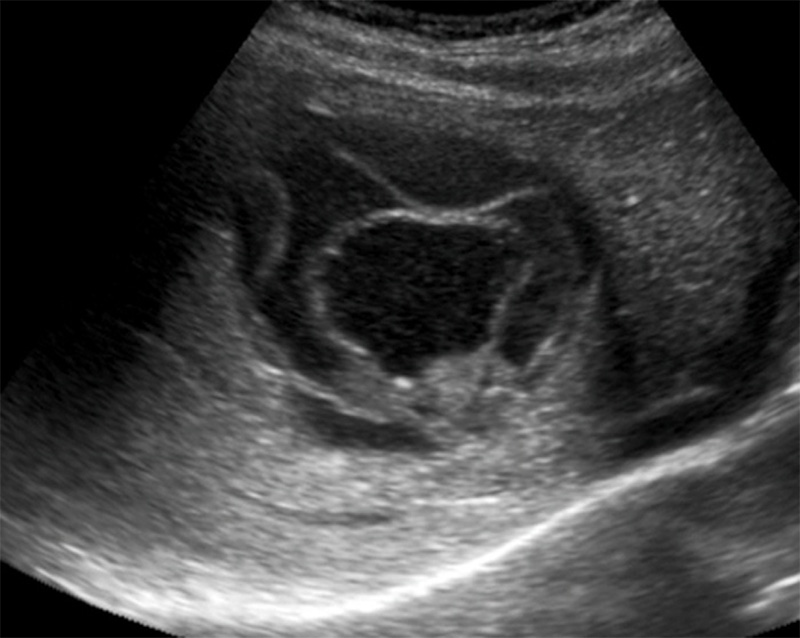

Figure 49. Mild hydronephrosis seen on long axis view of the kidney. Note the mild dilation of the renal pelvis and calyces and the lack of color Doppler flow over the anechoic (black) dilation of the renal pelvis.

Figure 50. Moderate hydronephrosis seen on long axis view of kidney without a change in the thickness of the renal cortex.